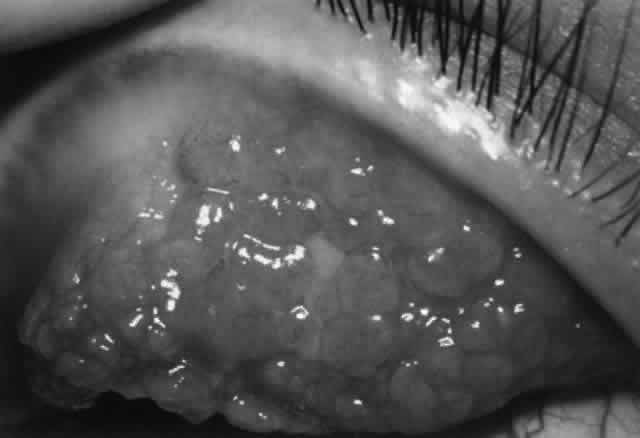

Type I: Immediate Hypersensitivity (Anaphylaxis) Type I hypersensitivity involves antigen binding to IgE bound to the surface of mast cells and subsequent cross-linking. This stimulates mast cell degranulation and release of preformed mediators (e.g., histamine). In addition, there is de novo synthesis of inflammatory mediators such as prostaglandins, leukotrienes, and PAF. The result is smooth muscle contraction, increased vascular permeability, and vasodilation. This is the predominant mechanism of allergic reactions and is discussed more fully elsewhere (see Mast Cells, and Allergic Conjunctivitis). Type II: Antibody-Dependent Cytotoxicity In type II reactions, complement-fixing antibody (e.g., IgM, IgG1, IgG2, IgG3) binds to the target cell. Complement then binds to this antibody, activating the classic pathway. The result is cell lysis. This is the pathogenic mechanism seen in Goodpasture's syndrome and in hemolysis in transfusion reactions. Pemphigoid, pemphigus, Mooren's ulcer, and thyroid-related orbitopathy are considered examples. Antibody-dependent cell-mediated cytotoxicity (i.e., K-cell activity) has also been categorized under type II reactions, although there is an obvious overlap with cell-mediated immunity. Type III: Immune Complex-Mediated Hypersensitivity (Arthus Reaction) Low levels of immune complexes are found in normal individuals as a result of antibody binding to antigen; these complexes are cleared by cells of the reticuloendothelial system. This process represents an effective mechanism of normal host defense. However, depending on certain factors (e.g., size of the immune complex, immunoglobulin class, antigen characteristics, hemodynamic turbulence), immune complexes can be deposited in tissues such as vascular walls and renal glomeruli. If these complexes contain IgM or IgG1–3, the complement cascade can be activated with release of chemotactic factors, neutrophil accumulation, and subsequent degranulation and enzyme release, causing local tissue damage. This mechanism is responsible for vasculitis and glomerulonephritis. Corneal immune ring formation is the result of immune complex deposition. Immune complex deposition was classically considered a major player in noninfectious uveitis; however, now its role is less clear. For example, Behçet's disease was thought to be the prototype of immune complex-mediated disease, yet T-cell-mediated mechanisms are also involved.12 Type IV: Cell-Mediated Hypersensitivity (Delayed Hypersensitivity) Type IV hypersensitivity was initially termed delayed hypersensitivity to describe those reactions that took more than 12 hours to develop. These reactions were found to be transferable to nonimmunized hosts by lymphoid cells but not serum, indicating the cell-mediated nature of this type of immune response. Classically, four types of type IV delayed hypersensitivity reactions have been described, based on characteristic skin reactions to antigen. These types include the Jones-Mote reaction, contact hypersensitivity, tuberculin-type hypersensitivity, and granulomatous inflammation. However, in practical terms, there is considerable overlap. To generalize, type IV cell-mediated hypersensitivity occurs as a result of class II-restricted antigen presentation by Langerhans cells or macrophages and IL-1 production, leading to helper T-cell stimulation and lymphokine release. This triggers a complex cellular response including recruitment of B cells, cytotoxic T cells, macrophages, and, to a lesser extent, neutrophils. Mechanisms of damage include cell-mediated cytotoxicity, phagocytosis, enzymatic processes, and, in the case of persistent antigen, epithelioid and giant cell formation (i.e., granulomatous inflammation). Type IV reaction plays a major role in virus infection, tuberculosis, leprosy, and fungal infection. Sympathetic ophthalmia and Vogt-KoyanagiHarada syndrome, corneal graft rejection, phlyctenulosis, and contact allergy are all type IV reactions. The Jones-Mote reaction is also known as cutaneous basophil hypersensitivity. It has been described as a unique form of type IV hypersensitivity in which there is a predominance of basophils. This form of hypersensitivity peaks at 24 hours, as opposed to contact and tuberculin reactions, which peak at 48 to 72 hours, and granulomatous reactions, which take 3 to 4 weeks to develop. It plays a role in vernal keratoconjunctivitis and contact lens-related giant papillary conjunctivitis (GPC). Type V: Stimulating Antibody Type V hypersensitivity is an antibody-mediated reaction in which autoantibody binds to cell receptors normally occupied by another molecule. This may lead to stimulation of the target cell (e.g., Graves' disease). AUTOIMMUNITY Tolerance Through its inherent specificity and through certain protective mechanisms, the immune system is able to differentiate self from nonself. Tolerance to self may be attained by removal of autoreactive T-cell clones during development (clonal deletion). Another possible mechanism is clonal anergy by which B cells are rendered unresponsive to self-antigen by exposure at an early stage of development. Other possible mechanisms include sequestration of autoantigen, absence of processing and presentation of self-antigen, receptor blockade by antigen, anti-idiotype antibodies, and activity of suppressor T cells that down-regulate potential autoreactivity.13,14 However, the safeguards of immunologic self-tolerance can malfunction, resulting in immune reactions against self (i.e., autoimmunity). Several mechanisms have been implicated. Mechanisms of Autoimmune Disease In normal persons, autoreactive B cells and T-effector cells and autoantigens are present; however, these are not normally active because autoreactive helper T cells are functionally absent.13 Under certain circumstances, functional autoreactive helper T cells may emerge either by dysfunction of suppressor cells or by the action of T-contrasuppressor cells (which enable anti-self helper T cells to resist suppression). Also, it is possible that in some cases autoantigen may bypass helper T cells altogether and directly stimulate T-effector cells and B cells. Also, suppressor T cells that normally prevent antibody production to self-antigen could become inactivated. Another possible autoimmune mechanism involves inappropriate expression of class II molecules on cells that normally do not possess this cell marker. This can occur in some diseases, especially in the presence of IFN-γ. This conveys to these cells the ability to act as antigen-presenting cells promoting inappropriate presentation of self-antigen. This may result in activation of helper T cells, leading to B-cell production of autoantibodies and/or activation of cytotoxic T cells. Cross-reactivity may play a role. Alteration of self-antigen (e.g., by drugs or viruses) may enable helper T cells to function as self-reactive T-helpers and thus to generate an autoimmune response. Alternatively, the normal T- and B-cell response to foreign antigen that possesses a structure resembling self-antigen may produce antibodies that cross-react with those self-antigens of similar structure. This is known as molecular mimicry. Nonspecific activation of the immune system by polyclonal activators (e.g., Epstein-Barr virus or bacterial lipopolysaccharides) may overwhelm normal immunoregulatory mechanisms and promote autoimmune disease. Anti-idiotype antibodies may normally play a role in controlling the immune response by binding the idiotype portion of surface immunoglobulin on B cells and suppressing B-cell antibody production. Dysfunction of anti-idiotype antibodies could lead to B-cell hyperactivity and could play a role in autoimmune disease. Some autoantibodies play a role in autoimmune disease by their effect on surface receptors. Autoantibodies can bind to cell-surface receptors and act as agonists. An example is Graves' disease, in which an autoantibody (long-acting thyroid stimulator [LATS]) binds to the thyroid-stimulating hormone (TSH) receptor, delivering the same stimulus as TSH and driving thyroid hormone production. Other autoantibodies can block cell-surface receptors, preventing binding of hormones or other molecules to their appropriate receptors and resulting in dysfunction. An example is myasthenia gravis, in which autoantibodies bind to acetylcholine receptors on the motor endplate, resulting in defective neuromuscular transmission. Genetic factors play a role in autoimmunity, as there are HLA associations with certain autoimmune diseases (e.g., Graves' disease and HLA-B8, -DRw3 in whites; ankylosing spondylitis and HLA-B27). Tissue injury in autoimmune disease may occur by a number of mechanisms. Type II reactions can be involved. Circulating autoantibodies may react with self-antigens on the cell surface, triggering complement activation and cell lysis via the membrane attack complex. Also, autoantibody binding can lead to activation of cytotoxic cells, resulting in cell lysis. A second mechanism involves type III reactions. Autoantibodies may bind to free antigen, forming circulating immune complexes that deposit in tissue, followed by complement activation and subsequent inflammation. Type IV (cell-mediated) hypersensitivity mechanisms also play a role in autoreactivity. IMMUNOSUPPRESSIVE AGENTS A classification of immunosuppressive agents is presented in Table 3. The mechanism of action of selected agents more commonly used in the treatment of ocular inflammatory disease is discussed.